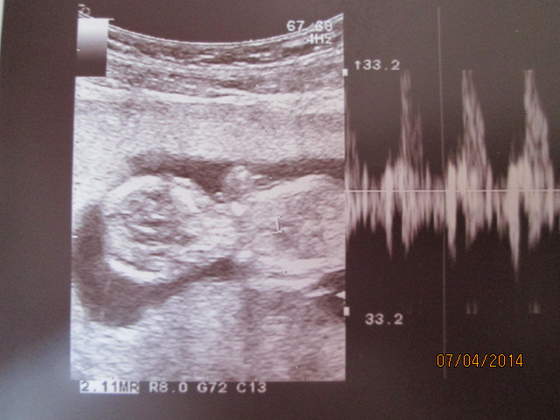

To i ja sie pochwale:-D moj dzidziol od tylu:-)